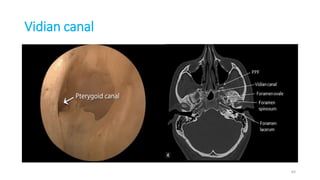

Vidian canal

64

VIDIAN CANAL-Pterygoid canal

152